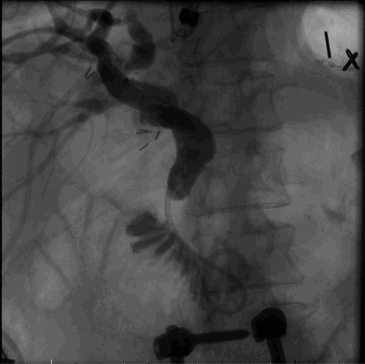

A 66-year-old Caucasian female with an extensive medical history, including heart disease, hyperlipidemia, and morbid obesity status post open Roux-en-Y gastric bypass in 1980 as well as an uncomplicated cholecystectomy, was referred to a hepatobiliary and pancreatic surgery practice at an academic tertiary care hospital by her family physician due to acute worsening of abdominal pain which had been gradually progressive over several months with intermittent nausea, vomiting, and acholic stools. The clinical exam was notable for right upper quadrant abdominal pain and jaundice. Laboratory evaluation was notable for total bilirubin 2.2 mg/dL, direct bilirubin 1.0 mg/dL, aspartate aminotransferase 90 IU/L, alanine aminotransferase 45 IU/L, alkaline phosphatase 208 IU/L, internal normalized ratio 1.2, and serum lipase 341 U/L. Imaging with computed tomography (CT) demonstrated intrahepatic and extrahepatic biliary dilatation with mild pancreatic ductal dilatation but no definite biliary or pancreatic lesion visualized (Figure 1).

Figure 1. The fluoroscopic image taken during placement of the percutaneous transhepatic catheter shows an extrahepatic biliary stricture in the mid-to-distal common bile duct with abrupt cutoff of contrast flow and upstream intra- and extrahepatic biliary dilatation.